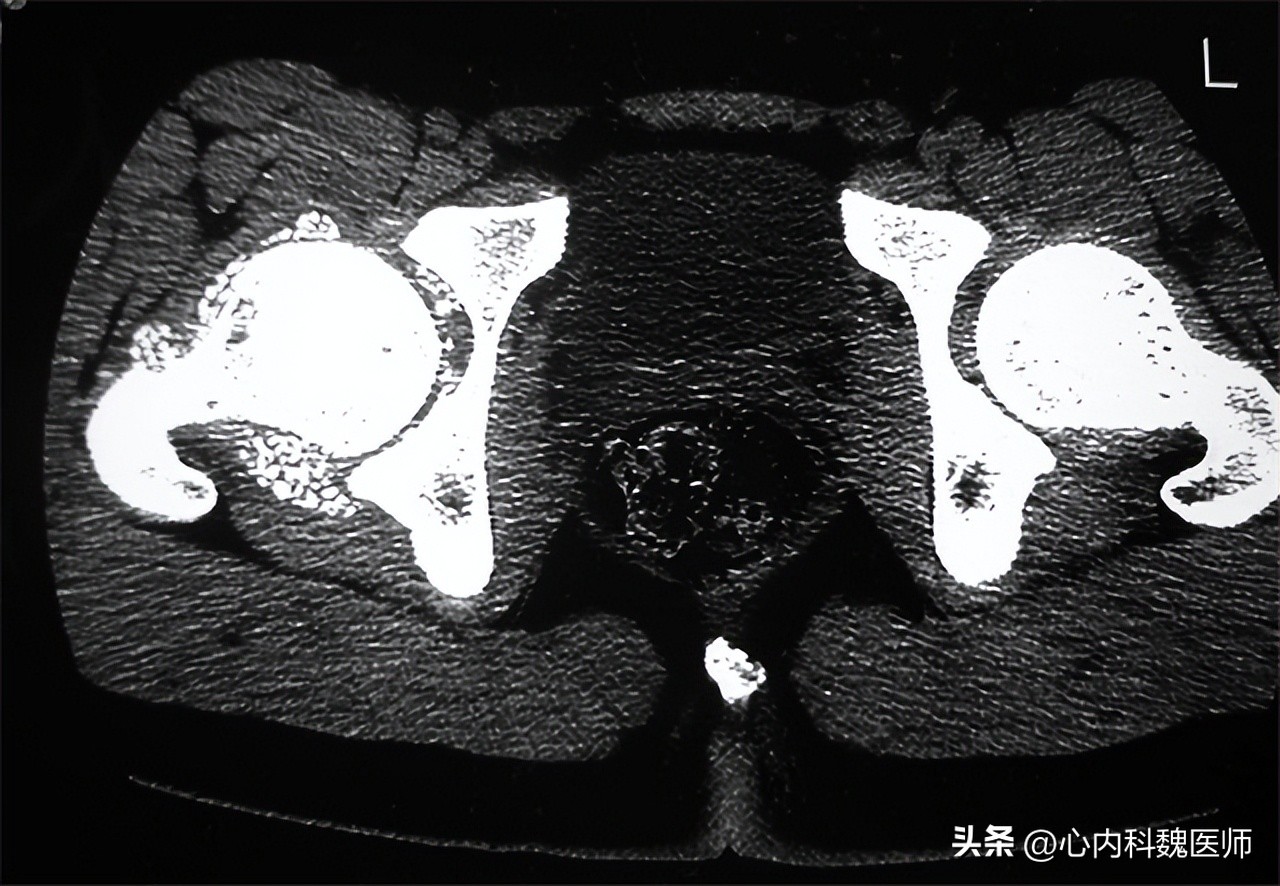

股骨头坏死相比以上两种疾病要严重许多,简单来说就是 股骨头部位的血液供应情况出现异常,导致血供中断或受损,从而引起股骨头组织及细胞的坏死。

股骨头坏死 早期患者主要表现为疼痛,常见于髋部、腹股沟区等部位 ,因此出现胯骨疼痛时,有可能是股骨头坏死。疼痛逐渐延伸并加重,放射到臀部、大腿、膝关节等部位。如果不及时进行治疗,患者会逐渐出现行走困难、间歇性跛行、功能障碍等,严重的患者疼痛剧烈,无法行走。

股骨头坏死使用药物治疗时,效果多不明显,只能起到延缓病情发展的作用。患 者一般采用手术治疗 ,保髋手术,通过修复髋关节功能,使股骨头内的血供恢复正常。还有一种就是现在很常见的 人工关节置换术 ,对于股骨头严重坏死的患者或是治疗效果不好的患者建议选择人工关节置换术。